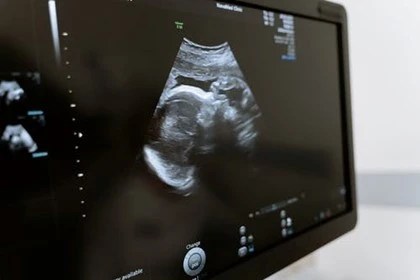

Obstetric and Gynecological Sonography

Specializing in obstetrics and gynecology will lead to qualifying as an OB/GYN, a specialist in women’s health. You’ll help patients identify a range of potential issues, but perhaps the most common (and highly rewarding) part of working as an OB/GYN is obtaining an ultrasound of a baby in the womb. This is an attractive role for many sonographers.